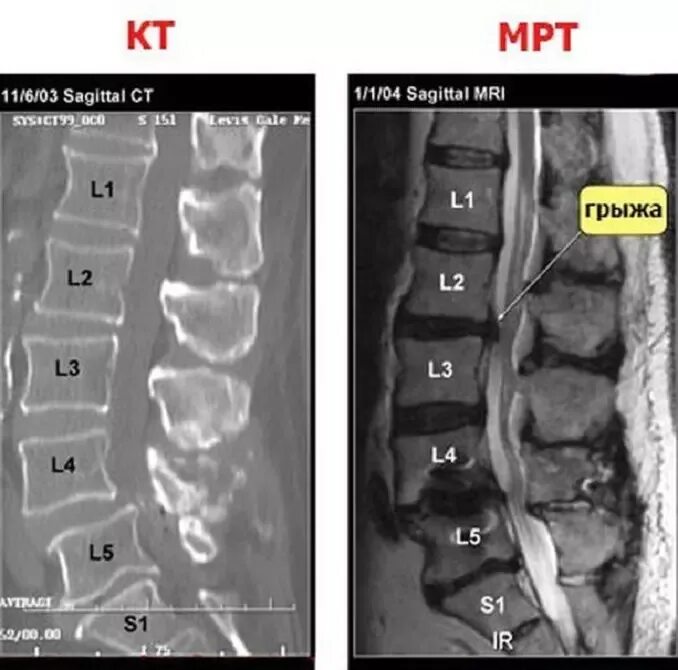

Есть мрт и кт